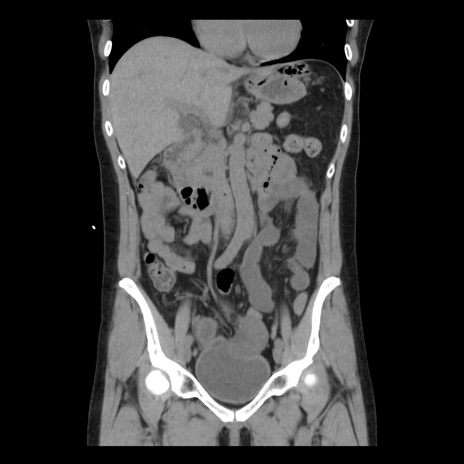

症例10(冠状断像)

【症例】 50歳代女性

【主訴】 腹痛

【現病歴】前日生レバーを食べた。今朝に排便あり。 昼前に突然発症の腹痛を生じ、当院救急外来を受診した。

【既往歴】 子宮筋腫にてで子宮全摘後

【身体所見】 意識清明、腹部:平坦、軟、下腹部やや左を中心に圧痛・反跳痛あり、筋性防御あり

【データ】WBC 7800、CRP 0.07